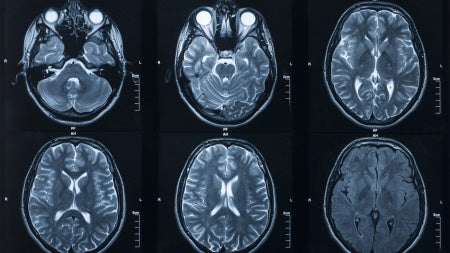

Most medical magnetic resonance imaging (MRI) scans are inherently qualitative, which can lead to subjective analysis and inconsistent conclusions.

“Our MR scan software analyzes images quantitatively and can be reproduced,” said Dan Ma, an assistant professor in the Department of Biomedical Engineering at the Case Western Reserve School of Medicine. “To understand qualitative versus quantitative diagnosis, consider a baby with a fever. Qualitative is touching the baby’s forehead and feeling that it’s hot. Quantitative is using a thermometer for a specific temperature reading. Images from qualitative MRI scans are hard to interpret objectively, reproduce and can vary based on the type of scanners even in the same hospital.”

The team will develop and validate a pipeline to implement the novel quantitative MR scanning technique MR Fingerprinting in the clinical workflow, and a quantitative image analysis software called MRF-QIA for MRF data analysis.

More specifically, the team is focused on demonstrating the scan and software’s effectiveness on measuring and predicting the spread of brain tumors in glioblastoma (GB) patients. GBs are highly aggressive brain tumors with a median survival of less than 15 months.

“Infiltration of cancer beyond the tumor margins causes recurrence in nearly 100% of GBs,” Badve said. “However, this cannot be measured by current MR imaging techniques, due to poor sensitivity and poor reproducibility when shared for analysis. The availability of reliable and reproducible infiltration prediction maps will lead to multi-site clinical trials in personalized radiation therapy and neurosurgery for improved patient outcomes.”